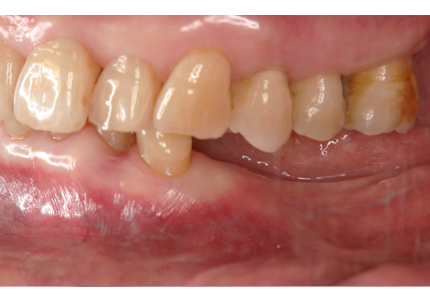

3.右上インプラント補綴物装着(2009年7月24日)

↑ 右上サイナスリフト後にインプラント埋入

4.左上下7番インプラント補綴物装着(2010年5月24日)